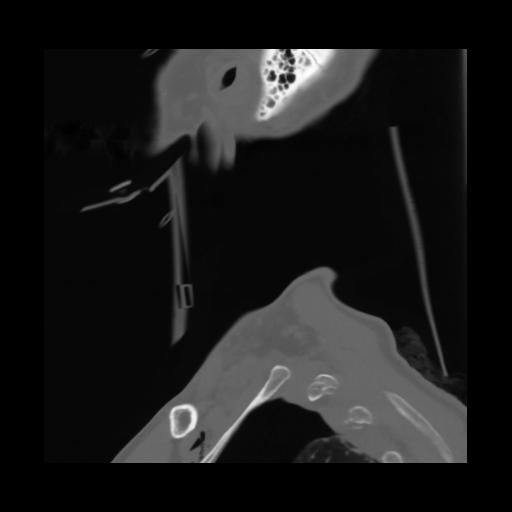

14 P.BLANDAS,,Sagittal,2.000,P.BLANDAS,Sagittal,